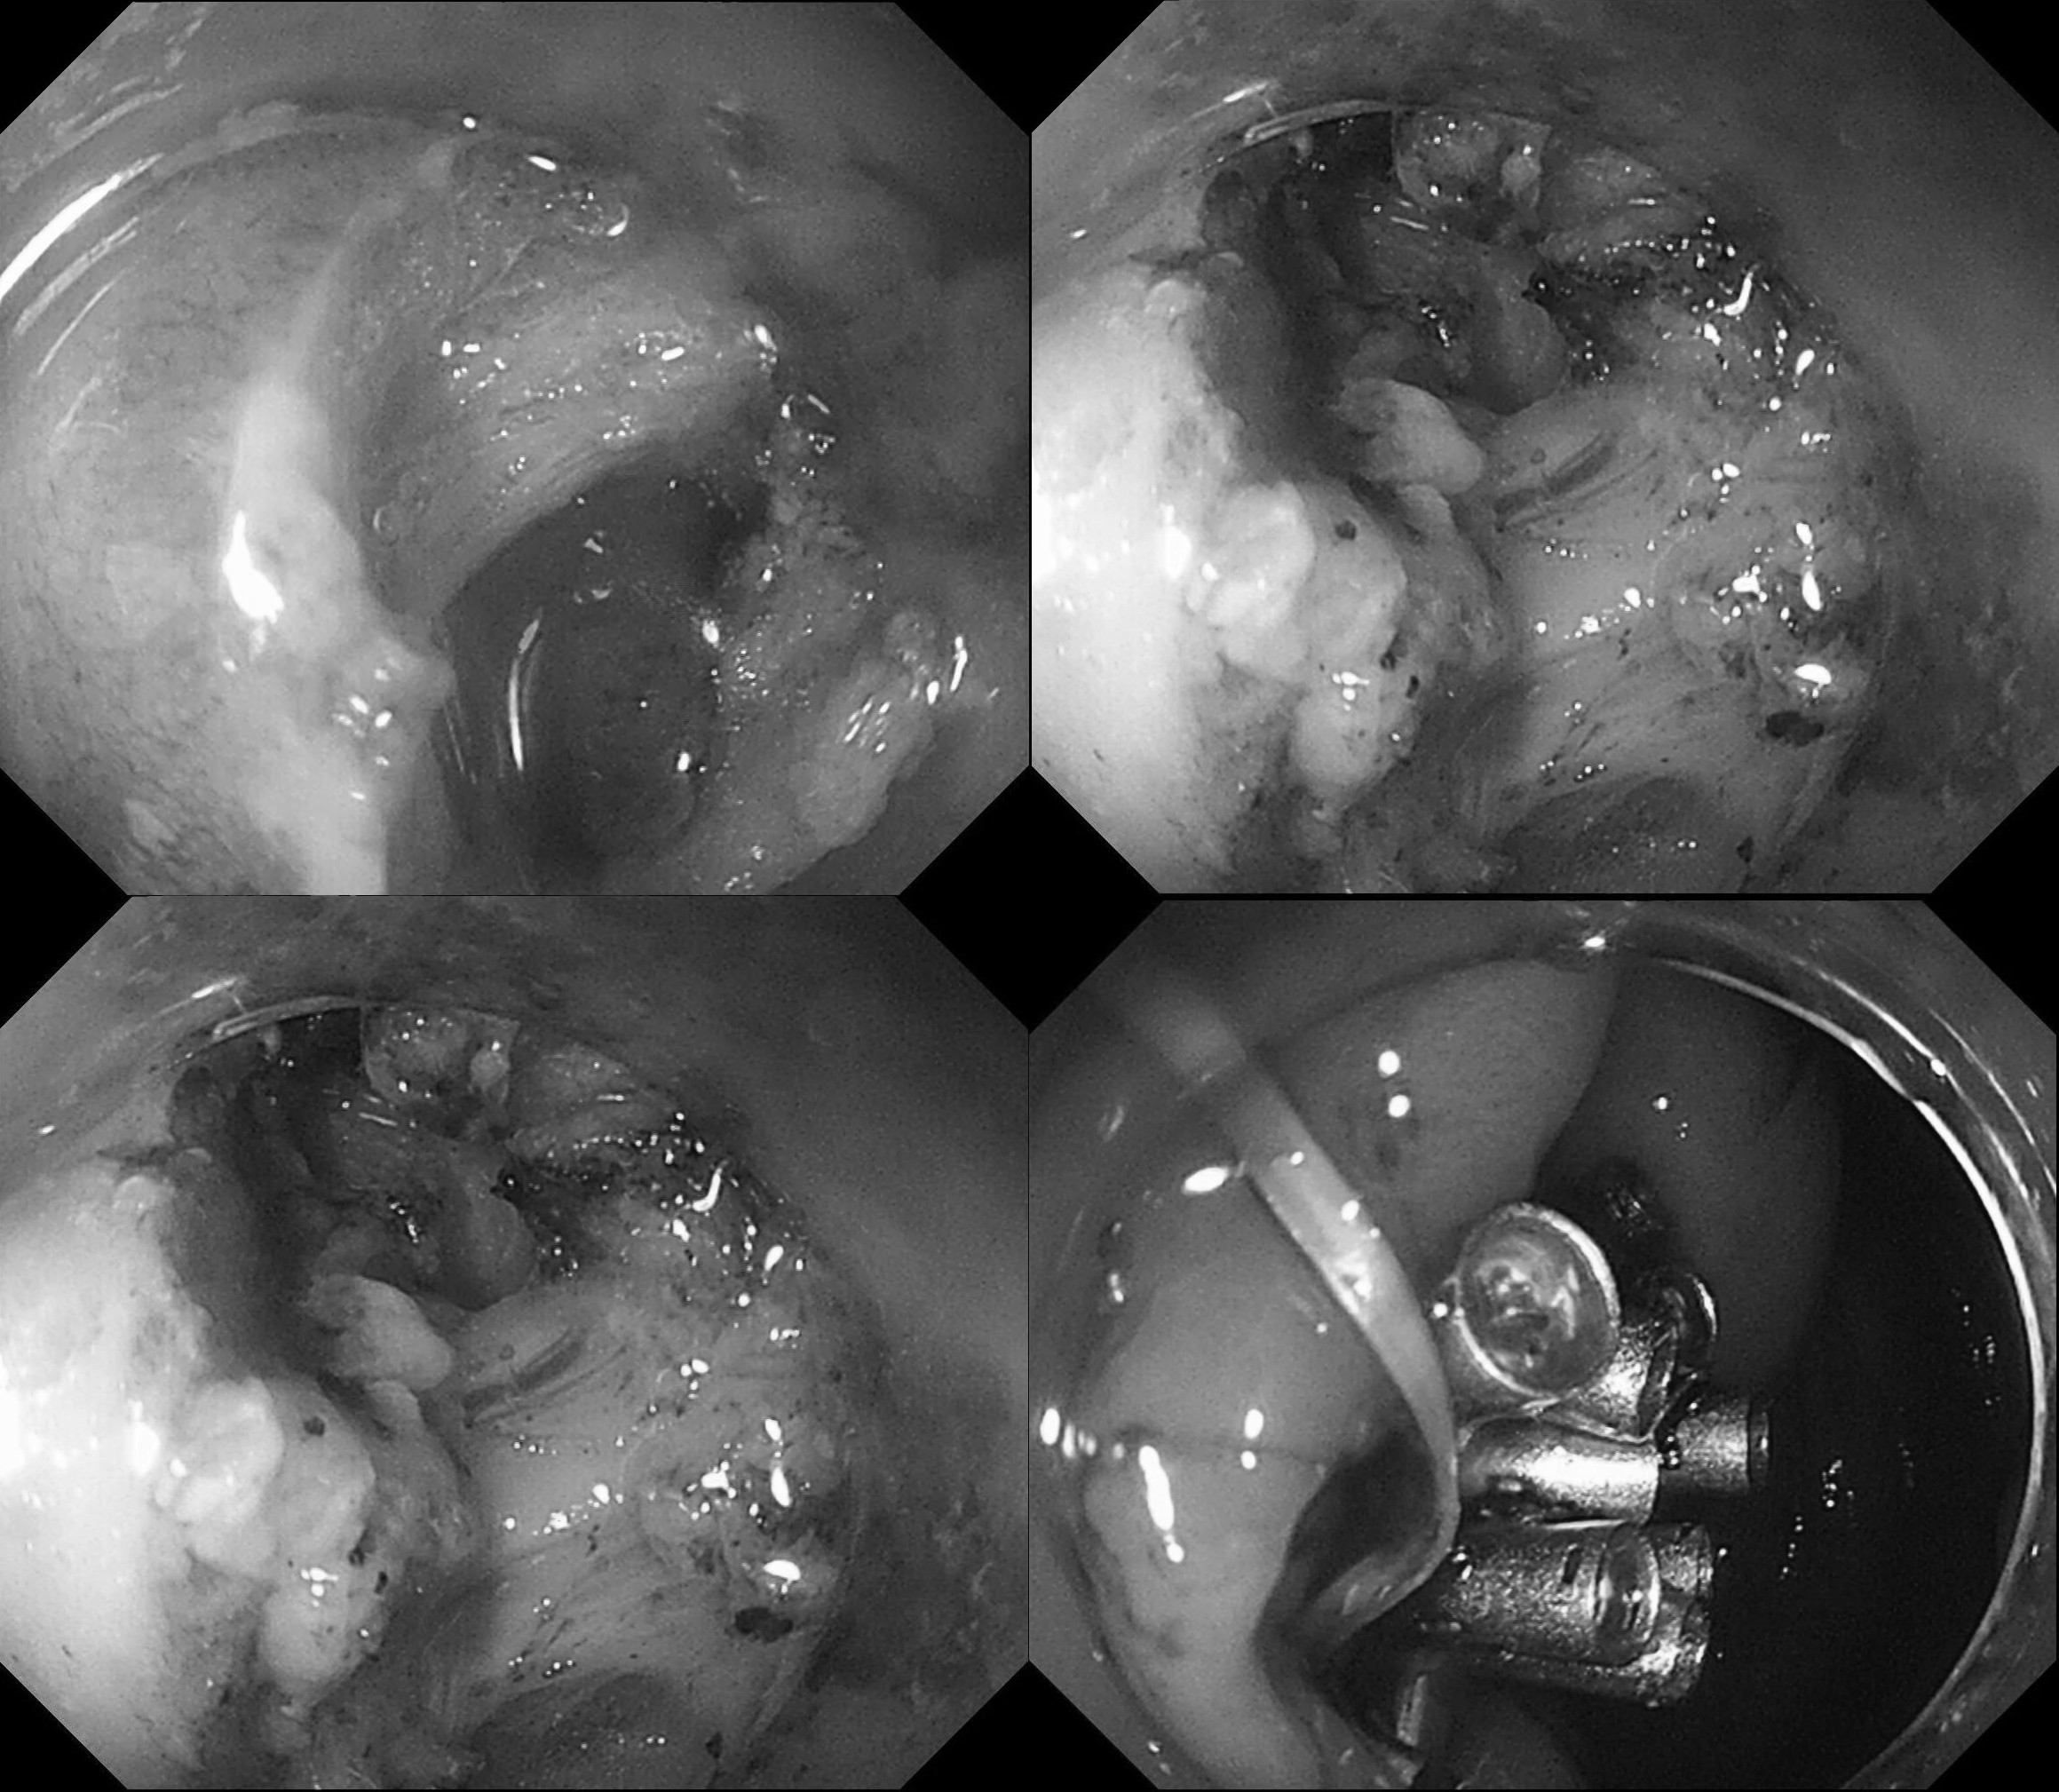

今下午两个病例 病例一:盲肠lst,esd术,顺利搞定. 病例二

图片尺寸1918x1306